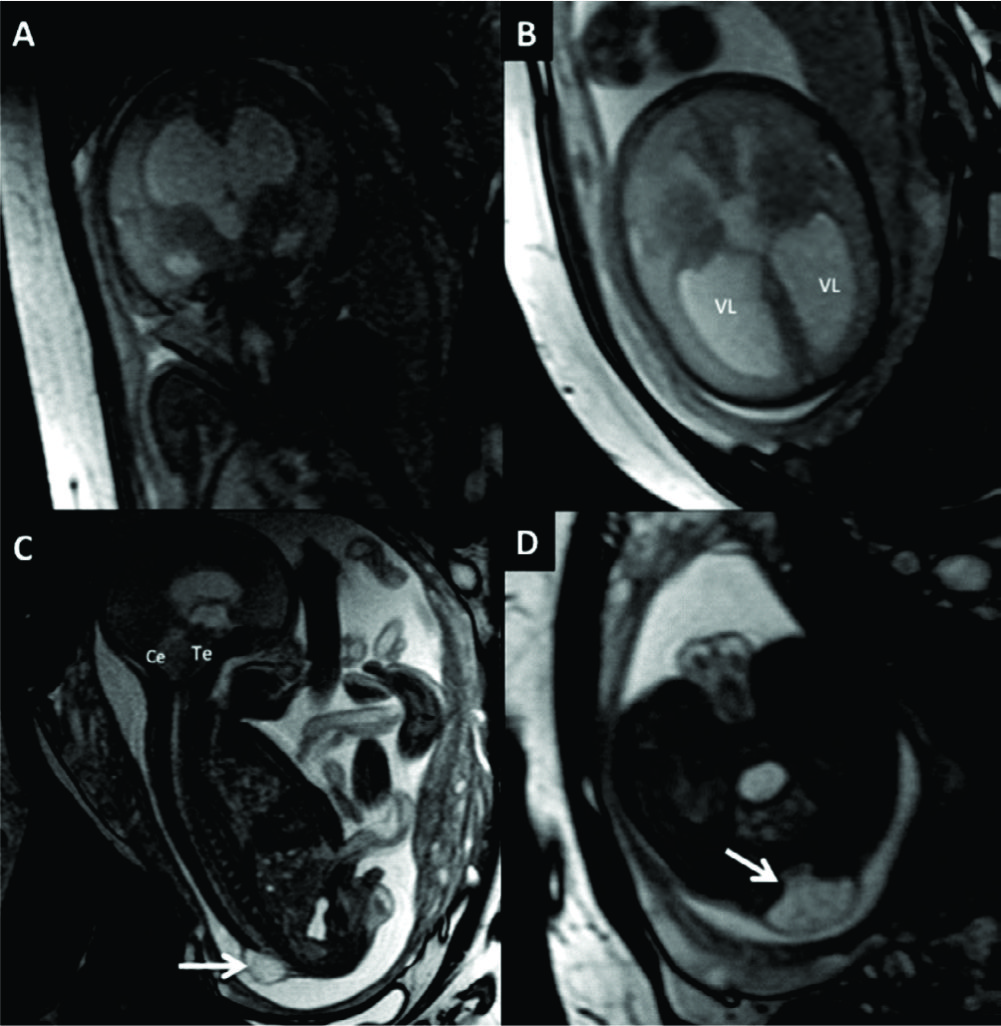

Figura 9

RM Fetal en Malformación de Fosa Posterior.

Se presentan 2 casos con diagnóstico de Dandy-Walker, ambos con malformación quística de la fosa posterior (è) comunicada con el IV ventrículo por alteración del desarrollo del vermis cerebeloso. En A y B imágenes sagital y axial de RMf realizada a las 27 semanas donde además se identifica dilatación del sistema ventricular supra-tentorial moderada. En el 2º caso (C y D) se observa una severa dilatación del sistema ventricular supra-tentorial con adelgazamiento del cuerpo calloso en un feto de 29 semanas de edad gestacional.

Te: Tronco encefálico

Ce: Cerebelo

Figura 10

RM Fetal en Malformación de Chiari.

Estudio realizado a las 29 semanas con diagnóstico ecográfico de mielomeningocele. En imagen coronal (A) se observa la severa dilatación del sistema ventricular supra-tentorial lo que se corrobora en la imagen axial (B) con una disposición colpocefálica de los ventrículos laterales (VL). En la imagen fetal sagital (C) se reconocen el cerebelo (Ce) y tronco encefálico (Te) sin identificarse claramente el IV ventrículo lo que indica una disminución de las dimensiones de la fosa posterior. En el mismo plano se observa el defecto de cierre posterior del tubo neural (è) con un saco de meningocele. La imagen axial a nivel de ese saco (D) muestra claramente el defecto espinal posterior (è) aunque sin observarse claramente el contenido neural del mismo.